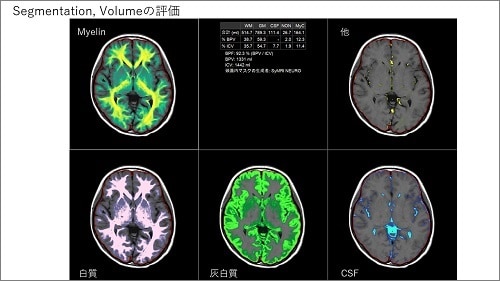

AI 技術の進化がもたらす頭部/頭頸部画像診断の新展開

頭部/頭頸部領域における、SmartSpeed AI の様々な臨床応用をご紹介いただきました。藤間先生が最近出版された 3 つの論文を引用されながら、SmartSpeed AI を脳 MRA、頭頸部 3D T1 強調画像、頭頸部 DWI(W.I.P)に対して適用した様々な画像を提示されました。SmartSpeed AI は、従来の Compressed SENSE 再構成や院内の他の 3T 装置と比較しても優れており、撮像の高速化と高画質化の双方で大変有用であると強調されました。

次に、SmartSpeed AI に対して、AI による超解像やリンギングアーチファクト除去も加えた技術(W.I.P)についてもご紹介されました。このような Dual type AI 再構成は、画質の高精細化によって、より詳細な画像評価が可能にすると述べられました。また、Single-shot 撮像に対して超解像を組み合わせることで、コントラストが良好な全脳高精細 T2WI 撮像を、たった 7 秒の撮像で達成できると紹介されました。このように、超解像技術を撮像時間短縮に応用するアプローチは、今後脳のルーチン検査を 1 分台まで短縮する可能性を持ち、会場でも大変話題になりました。